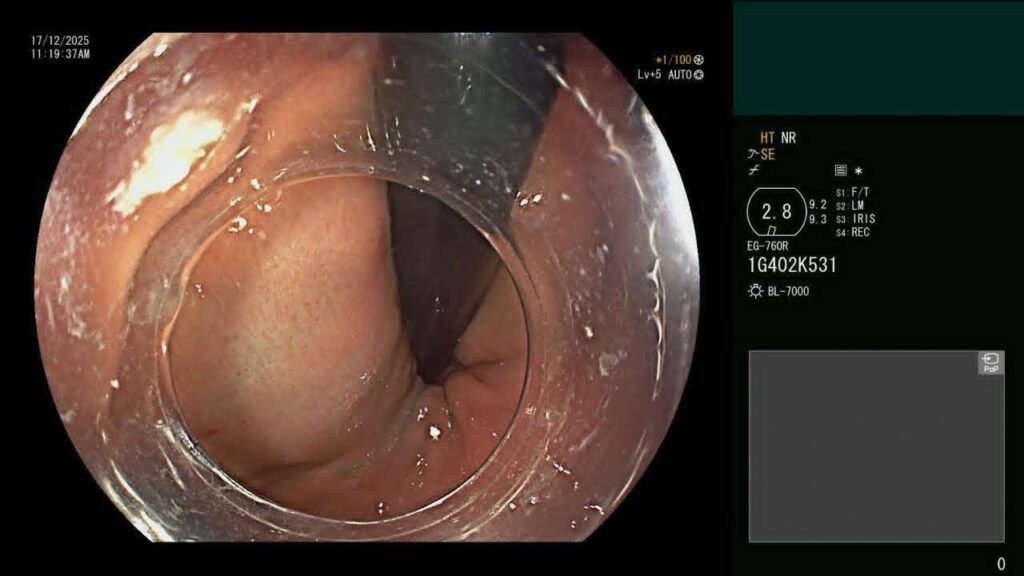

أجرى قسم جراحة الأطفال بالتعاون مع قسم الجهاز الهضمي والكبد بمستشفى سيد جلال الجامعي بطب الأزهر عملية تدخل علاجي دقيق بتقنية شق عضلة المريء بالمنظار (Per Oral Endoscopic Myotomy – POEM) لطفلة تبلغ من العمر عامين فقط وبوزن ٩ كجم؛ حيث عانت الطفلة من قيء مستمر، وصعوبة شديدة في البلع، وتأخر ملحوظ في النمو إلى أن تم حجزها والاعتناء بحالتها بقسم جراحة الأطفال بمعرفة د/أحمد أبو الحسن، صاحب الدراسة البحثية لعلاج حالات أكاليزيا الأطفال بالمنظار، تحت إشراف أ.د /إبراهيم جمعان، رئيس وحدة مناظير جراحة الأطفال، ثم تم إجراء العملية بوحدة مناظير الجهاز الهضمي بقسم الكبد والجهاز الهضمي، بالتعاون مع فريق قسم جراحة الأطفال، والتي استغرقت نحو ٣٠ دقيقة فقط، بنجاح تام دون حدوث أي مضاعفات أثناء أو بعد إجراء العملية، مع تحسن ملحوظ وسريع في البلع، وخروج الحالة بسلام من قسم جراحة الأطفال بعد التأكد من نجاح التدخل واستقرار الحالة العامة.

وتُعد هذه الحالة Case Report علميًّا؛ حيث تُصنف باعتبارها من الحالات النادرة التي يتم فيها تطبيق تقنية POEM لطفل يقل عمره عن ٣ سنوات ووزنه أقل من ١٠ كجم، وهو ما يمثل إضافة علمية وطبية متميزة باسم مستشفيات جامعة الأزهر بما يعزز من مكانة الجامعة إقليميًّا ودوليًّا في مجال مناظير الجهاز الهضمي العلاجية المتقدمة والتدخلات فائقة الدقة بالمنظار.